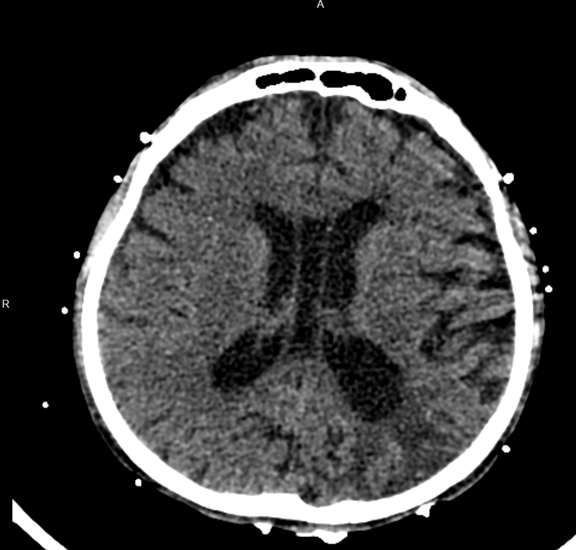

Imaging included a non-contrast head computed tomography (CT) that demonstrated a left posterior parietal infarct of indeterminate age, without signs of acute ischemia or hemorrhage. Echocardiography revealed a severely reduced left ventricular ejection fraction (25–30%) with severe global hypokinesis, moderate right ventricular dilation with systolic dysfunction, and moderate mitral and tricuspid regurgitation. These findings were consistent with decompensated cardiogenic shock in the setting of mitochondrial cardiomyopathy. The patient was transferred to the intensive care unit (ICU) and intubated for encephalopathy and respiratory failure. He initiated continuous renal replacement therapy (CRRT) for anuric renal failure and volume overload.

Figure 1: CT scan of a 44-year-old MELAS patient showing infraction and ischemic changes